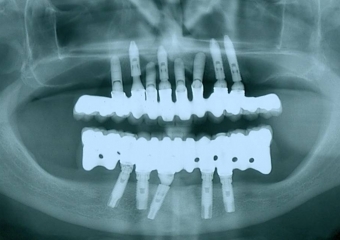

Raio X com implantes Cone Morse e próteses fixas em porcelana